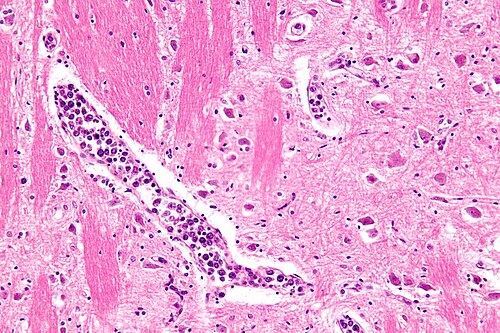

57 year old woman. Multi-organ dysfunction and stroke.

Pons. Intermediate magnification. H&E stain.

leukemia (blast crisis)

WBC significantly elevated.

It looks intravascular and lymphoid.